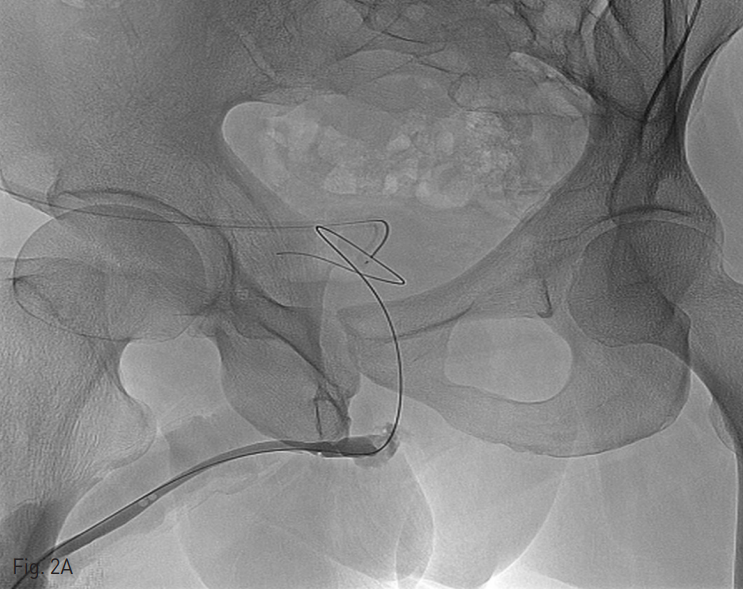

Fig. 2

B. A 14-F Foley catheter is inserted into the bladder over the wire.

5 Fr catheter (KMP, Cook, Bloomington, Indiana)을 요도 입구에 삽입한 다음, 2% lidocaine 10mL을 catheter 내로 주입하여 국소 마취를 시행 하였다. 요도 손상 부위 및 정도를 평가하기 위해 조영제를 주입하여 역행성 요로 조영술을 시행하였다. 투시 유도 하에, 0.035 인치 유도 철사 (Terumo, Tokyo, Japan)가 탑재된 catheter을 요도 입구에 삽입하고, 손상된 요도를 지나갈 때까지 이를 조정하였다. 일단 유도 철사가 손상 부위를 지나면, 유도 철사를 방광까지 넘긴 다음 이를 따라 catheter을 방광까지 넘겼다. 그리고 나서 유도 철사를 제거하고, 조영제를 catheter 내로 주입하여 catheter 끝이 방광 내에 있음을 확인한 후, 0.035인치 딱딱한 유도 철사 (Terumo, Tokyo, Japan)을 catheter내로 삽입하여 이 유도 철사를 방광내에 말아 놓았다. Catheter을 제거한 다음, 0.035인치 딱딱한 유도 철사를 따라 14 Fr 요도관을 삽입하는데 성공 하였다.